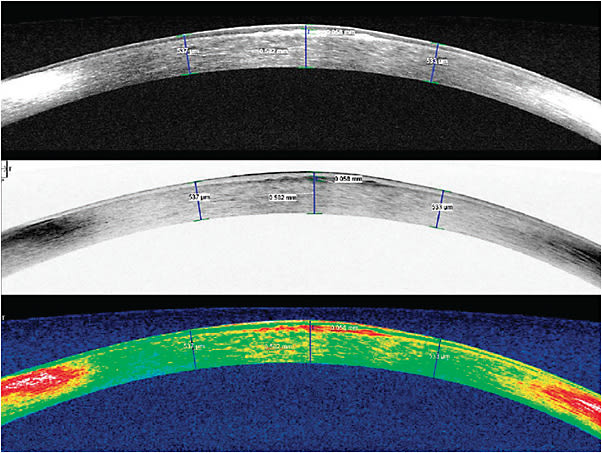

The patient was diagnostically fitted with a scleral lens (Figure 2), and the best-corrected visual acuity (BCVA) was 20/60. This was somewhat less than anticipated based on the slit lamp exam. Anterior segment optical coherence tomography (AS-OCT) showed a subepithelial scar with a thickness of about 60 microns at the level of Bowman’s layer (Figure 3). We suspect that the less-than-anticipated BCVA may be related to the subepithelial scar.

The patient was referred to a cornea specialist/ophthalmic surgeon for a possible superficial keratectomy or excimer laser phototherapeutic keratectomy (PTK) to remove the subepithelial scar.

This case illustrates the value of AS-OCT in helping to identify a central corneal scar that we missed during our initial slit lamp examination. CLS